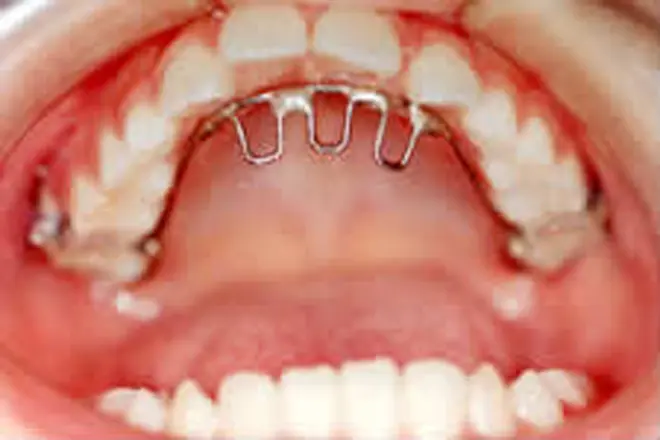

子どもの矯正 治療例3

左上の前歯が歯肉に埋まったケースです。

埋まっていた前歯を外科的に露出させました。

矯正装置を装着し、正しい位置へと移動させます。

前歯が正しい位置に移動してきました(治療中です)。

| 患者さまの年齢・性別 | 8歳・男性 |

| 治療期間 | 8ヵ月 |

| 治療費(税込) | 165,000円 |

| 主訴 | 左上の前歯が出てこない |

| 診断名・主な症状 | 上顎左側中切歯の埋伏 |

| 治療に用いた主な装置 | 表側矯正装置 |

| 治療内容 | 歯肉を切開し、埋もれている歯が見えるようにしました。装置を付けて所定の位置まで引っ張り出して歯並びを整えます。 |

| 抜歯部位 | 非抜歯 |